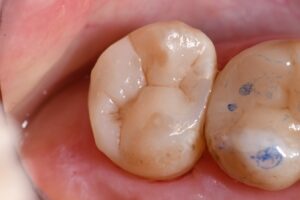

Please find attached the revised composite restoration for tooth #15/2.7 DOB retaining the mesial wall. A single shade of A3 Voco Grandio SO was used with the matrix in matrix system in place on the DOB and is slated to perform well in this high load region due to its intrinsic compressive strength of 439MPa. A post-operative radiograph is attached for reference.